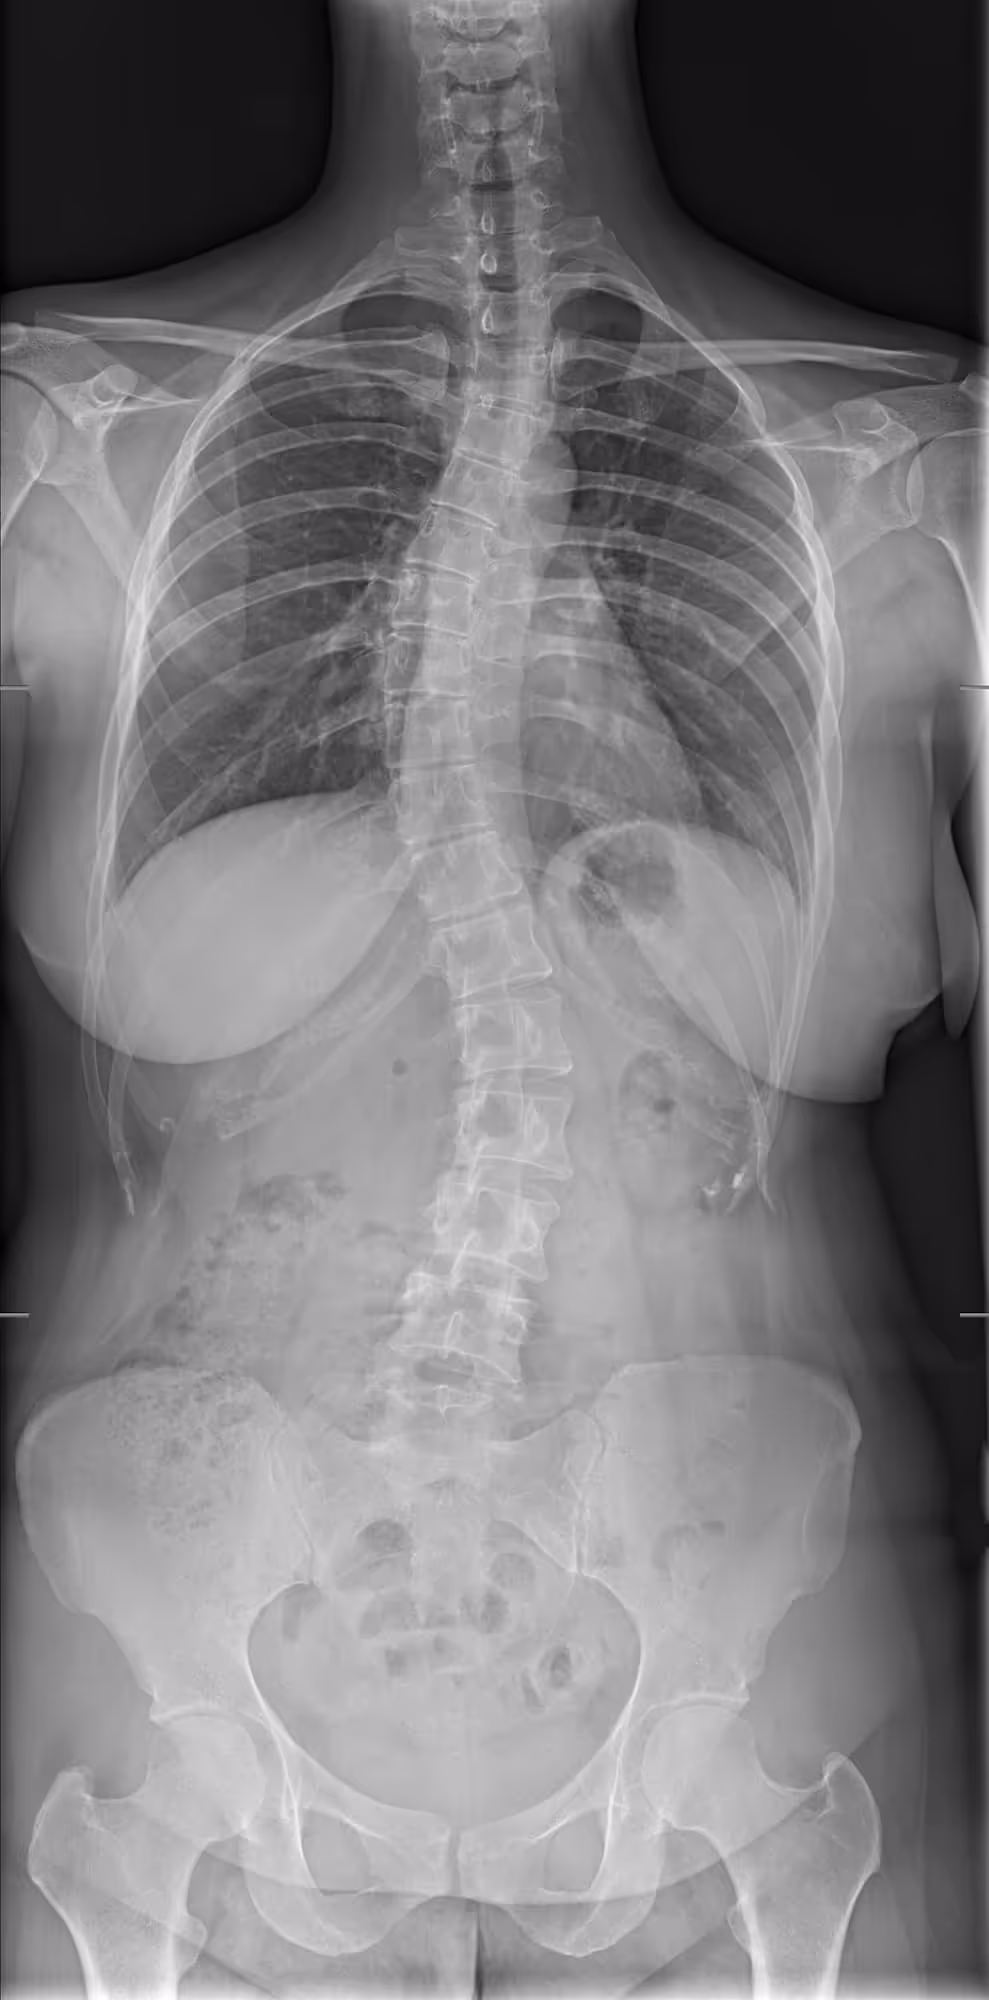

A 30-year-old woman with dorsal pain

BoneMetrics revealed a confirmed diagnosis of triple curve scoliosis

BoneMetrics automates MSK measurements with precision, covering scoliosis. It streamlines workflows on X-ray acquisitions, enabling faster, more accurate diagnoses for improved patient care.

Deep learning algorithm enables automated Cobb angle measurements with high accuracy

Hayashi D, Regnard N-E, Ventre J, Marty V, Clovis L, Lim L, Nitche N, Zhang Z, Tournier A, Ducarouge A, Kompel A J, Tannoury C, Guermazi A